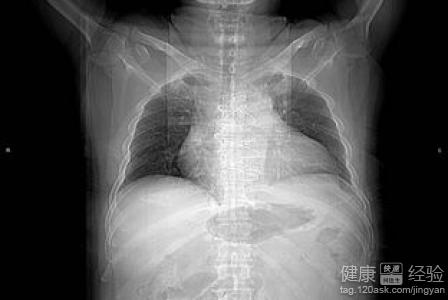

3最後。對於心髒擴大,常見於高血壓和主動脈瓣病變,表現為左心尖向左下延伸,心腰凹陷,主動脈結突出,心影呈靴型, 常見於心肌炎、全心衰竭、心包積液等。表現為心影向兩側增大。